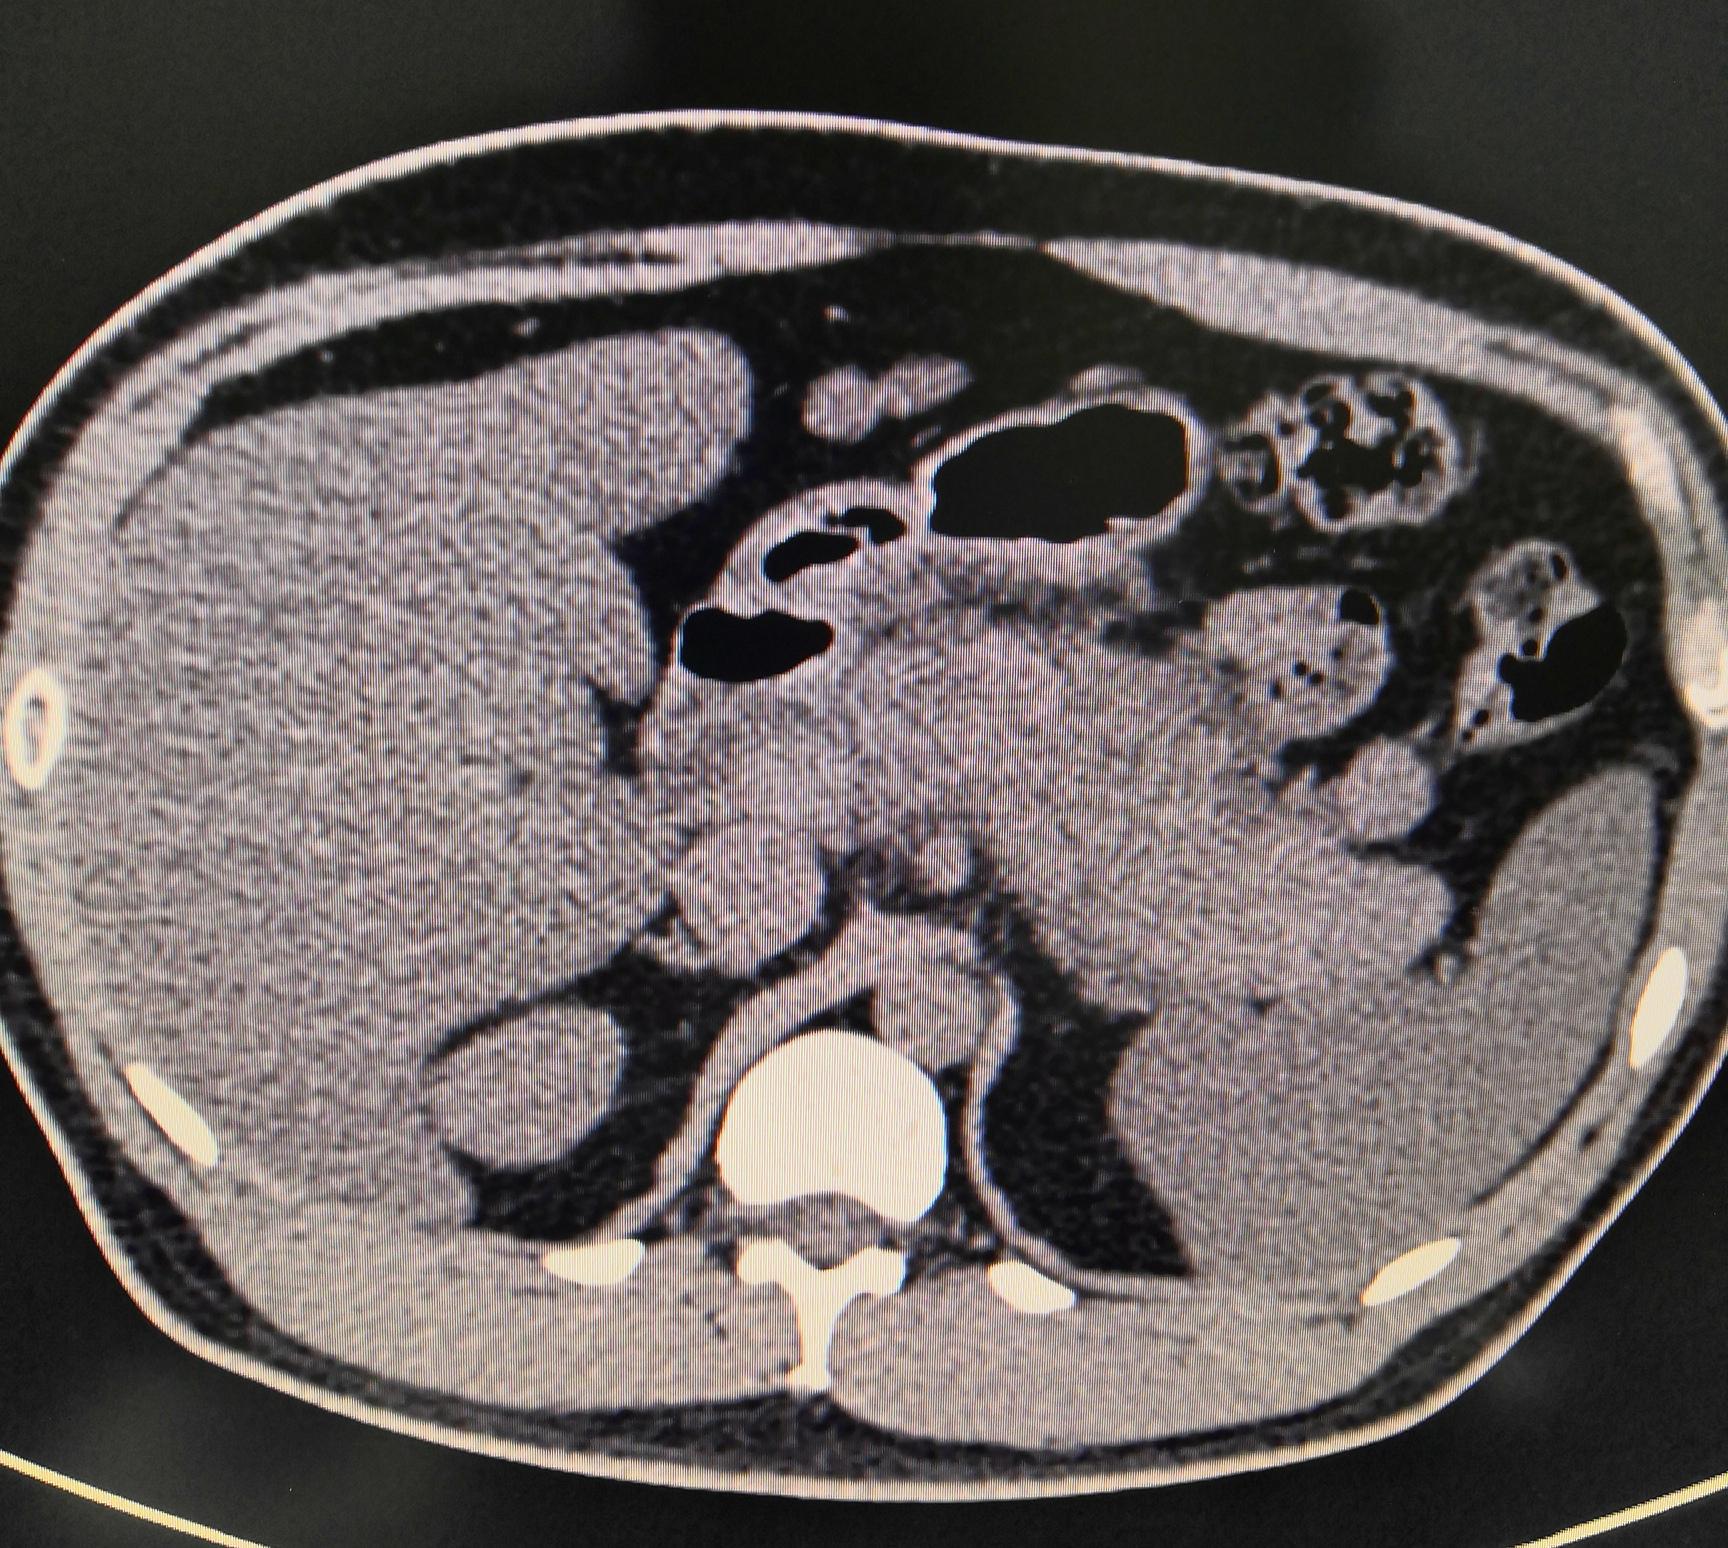

CT检查可以明确观察胰腺是否有肿胀、密度高低情况、是否伴有假性囊肿、胰腺周围脂肪间隙情况以及肾前筋膜是否增厚,从而判断炎症发生的位置、渗出情况、炎症的类型以及辅助判断病因等,同时,还可以指导临床分级,为后续医生治疗方案的确定提供可靠的前提基础。至于该怎么治疗,只能因人而异,因病情而异,最终还是要听临床医生的了。反正身体不舒服别硬抗,应及时到医院检查,否则小病变大病神医也难妙手回春!